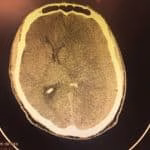

- Fratura do crânio

- Tratamento de fraturas do crânio

- Correção de fístula liquórica do crânio